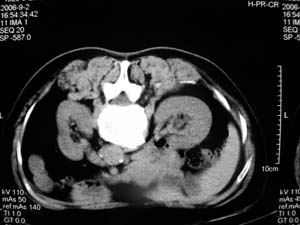

标题: DSA0075:[原创]肾囊肿穿刺硬化术 [打印本页]

标题: DSA0075:[原创]肾囊肿穿刺硬化术

我们主要在ct引导下进行各种囊肿的穿刺引流,对于肾囊肿治疗的较多.穿刺成功后尽量抽尽囊液并且记录数量,抽尽后注入造影剂看看是否与尿路相通,然后用1/4的比例注入无水酒精进行硬化.跟踪观察治愈率达98%以上.